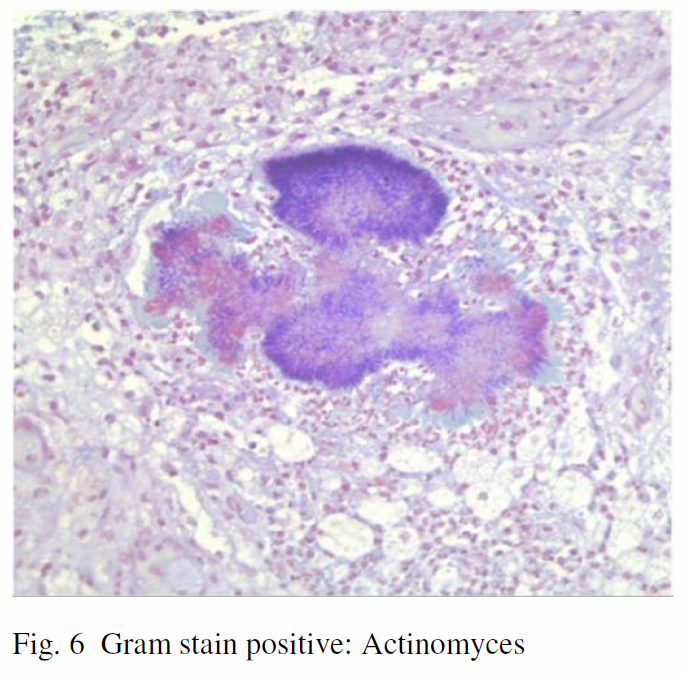

Multiple colonies of Gram and Grocott stain positive filamentous organisms were identified to be Actinomyces. (Fig. 6) Intraoperative swab from an abscess grew bacteriodes and sputum grew Enterobacter. Intravenous Tienam was started and was later switched to Pen G after two weeks. Pen G was given for another two weeks and she was eventually discharged with 8 months of Augmentin. Multiple dental caries were later identified and with extractions done by dental surgeon. Marked resolution of her right upper lobe infiltrate was found after 9 months of treatment.